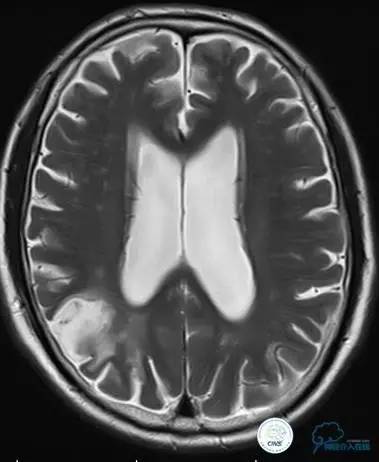

患者:49岁男性,左侧偏瘫1个月,药物治疗、康复训练效果不好,转我院,肌力0~1级。

core-clilnical明显不匹配,是介入开通的合适患者。

造影评价血管、判断闭塞段,微导丝谨慎穿过闭塞段,微导管造影,交换技术,球囊扩张,Enterprise支架。在后扩张时导丝刺破M3段血管,蛛网膜下腔出血(SAH)。

微导管进入破裂血管,栓塞弹簧圈1枚,出血停止,结束手术。继续双抗,术后2天肌力2级,神经功能恢复明显加快。

术后即刻和6天后CT,患者无明显临床症状。

半年后复查造影,无支架内再狭窄,可见弹簧圈,患者恢复至自己柱杖行走。